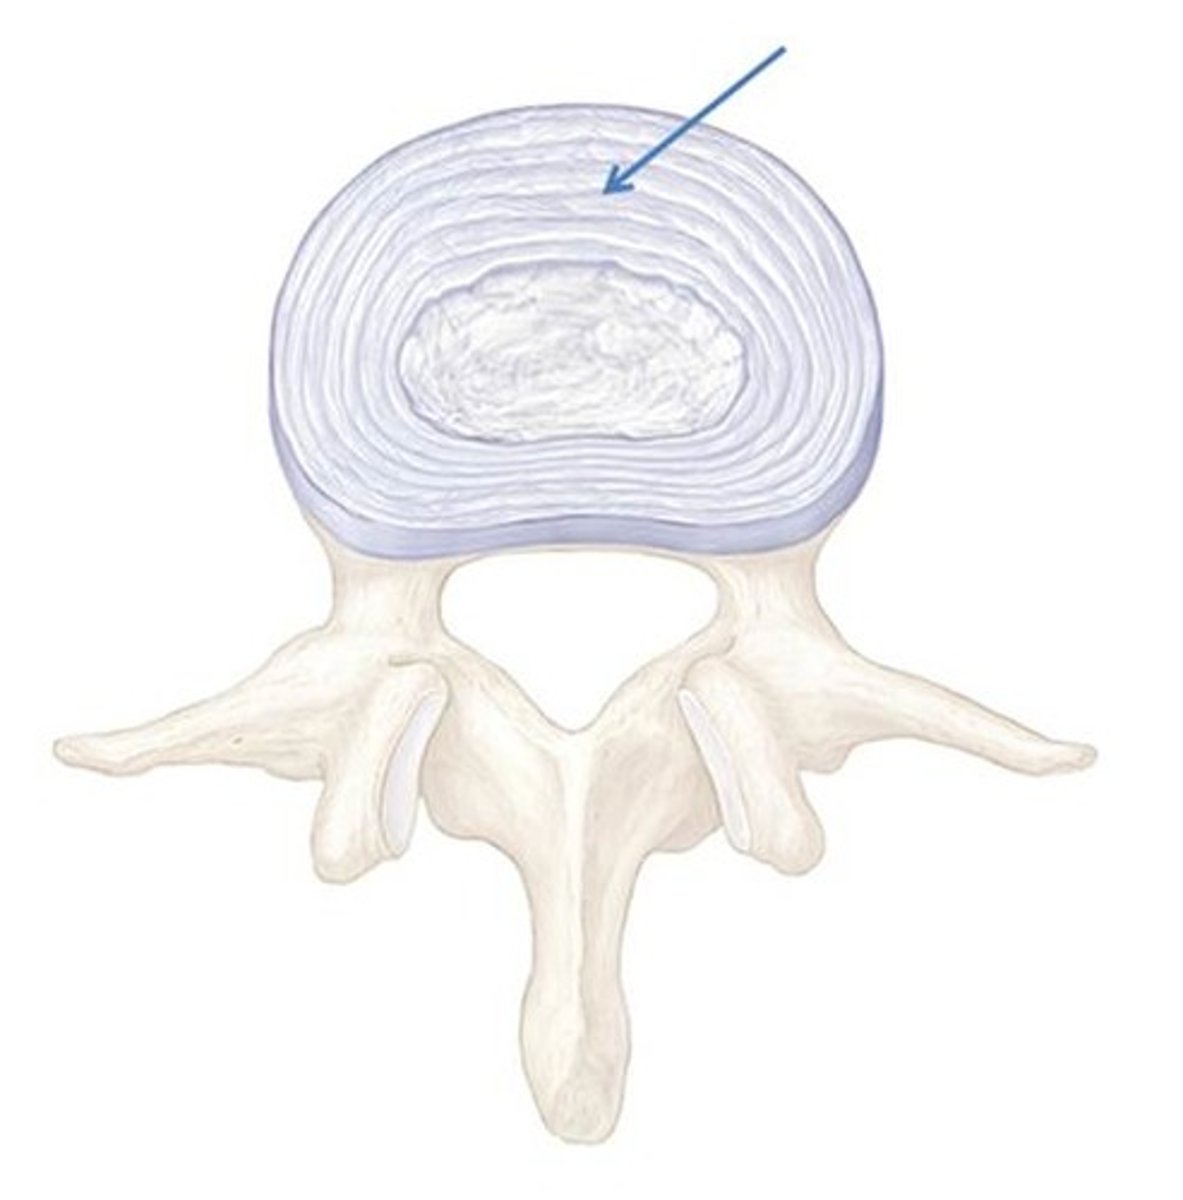

anulus fibrosus

nucleus pulposus

Shock absorbtion

what is the purpose of the intervertrebral disks